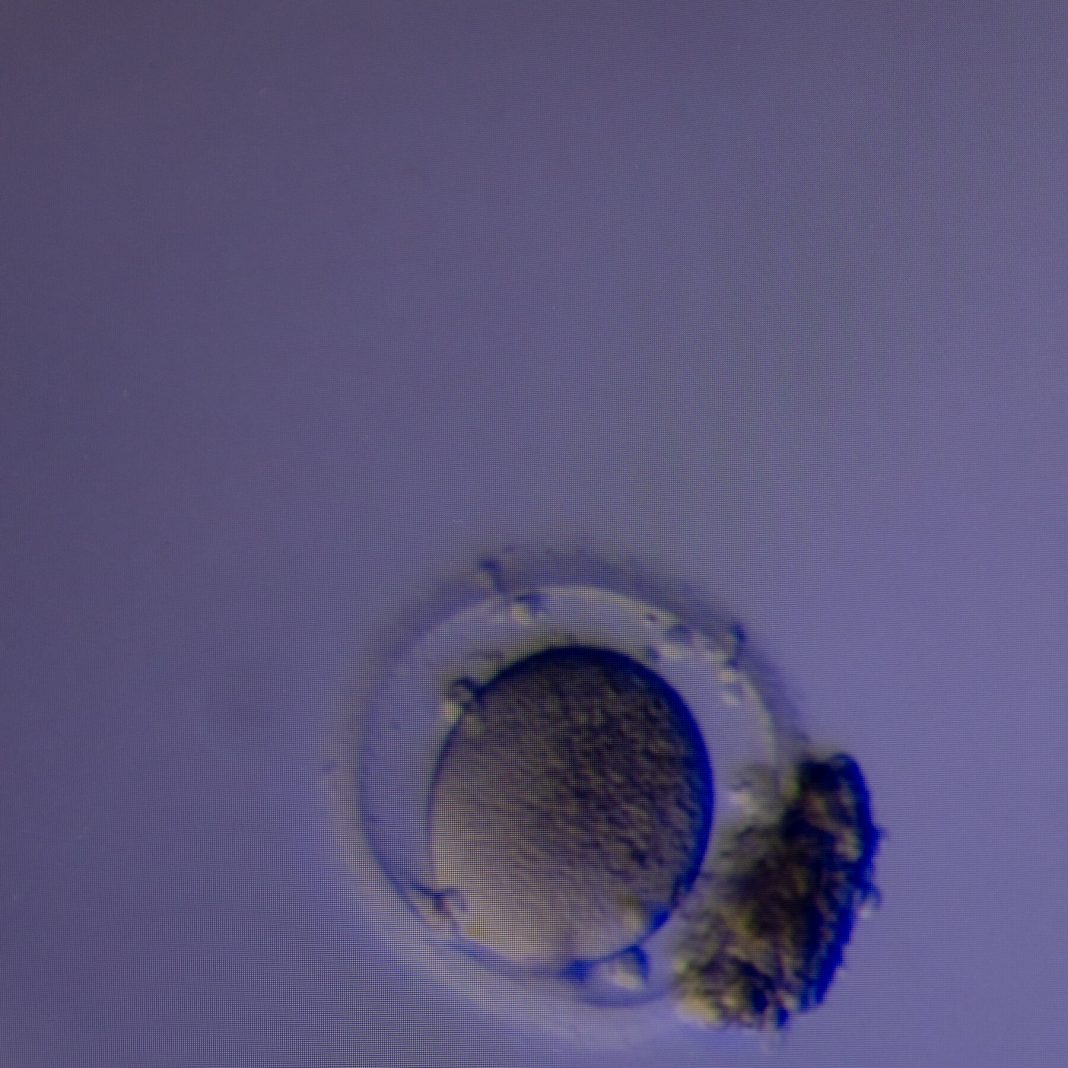

New Method Can Find Hidden Eggs to Aid in Fertility Treatment

A study reported that the conventional method of searching follicular fluid didn’t find all the eggs. The new technology found extra eggs more than half the time.